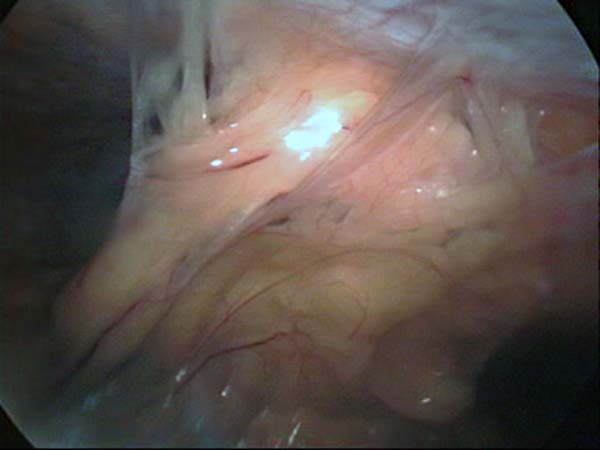

Photos laparoscopie Kyste ovarien Cystectomie ovarienne Septum utérin Grossesse tubaire